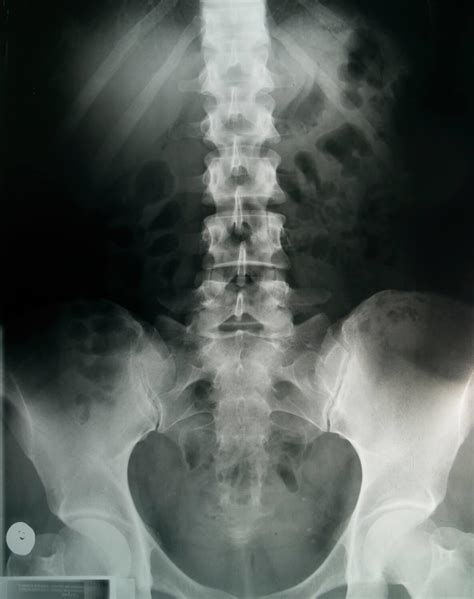

• Imaging Studies: An MRI is the "gold standard" for viewing the soft tissue of the disc, while X-rays may be used to rule out bone issues.